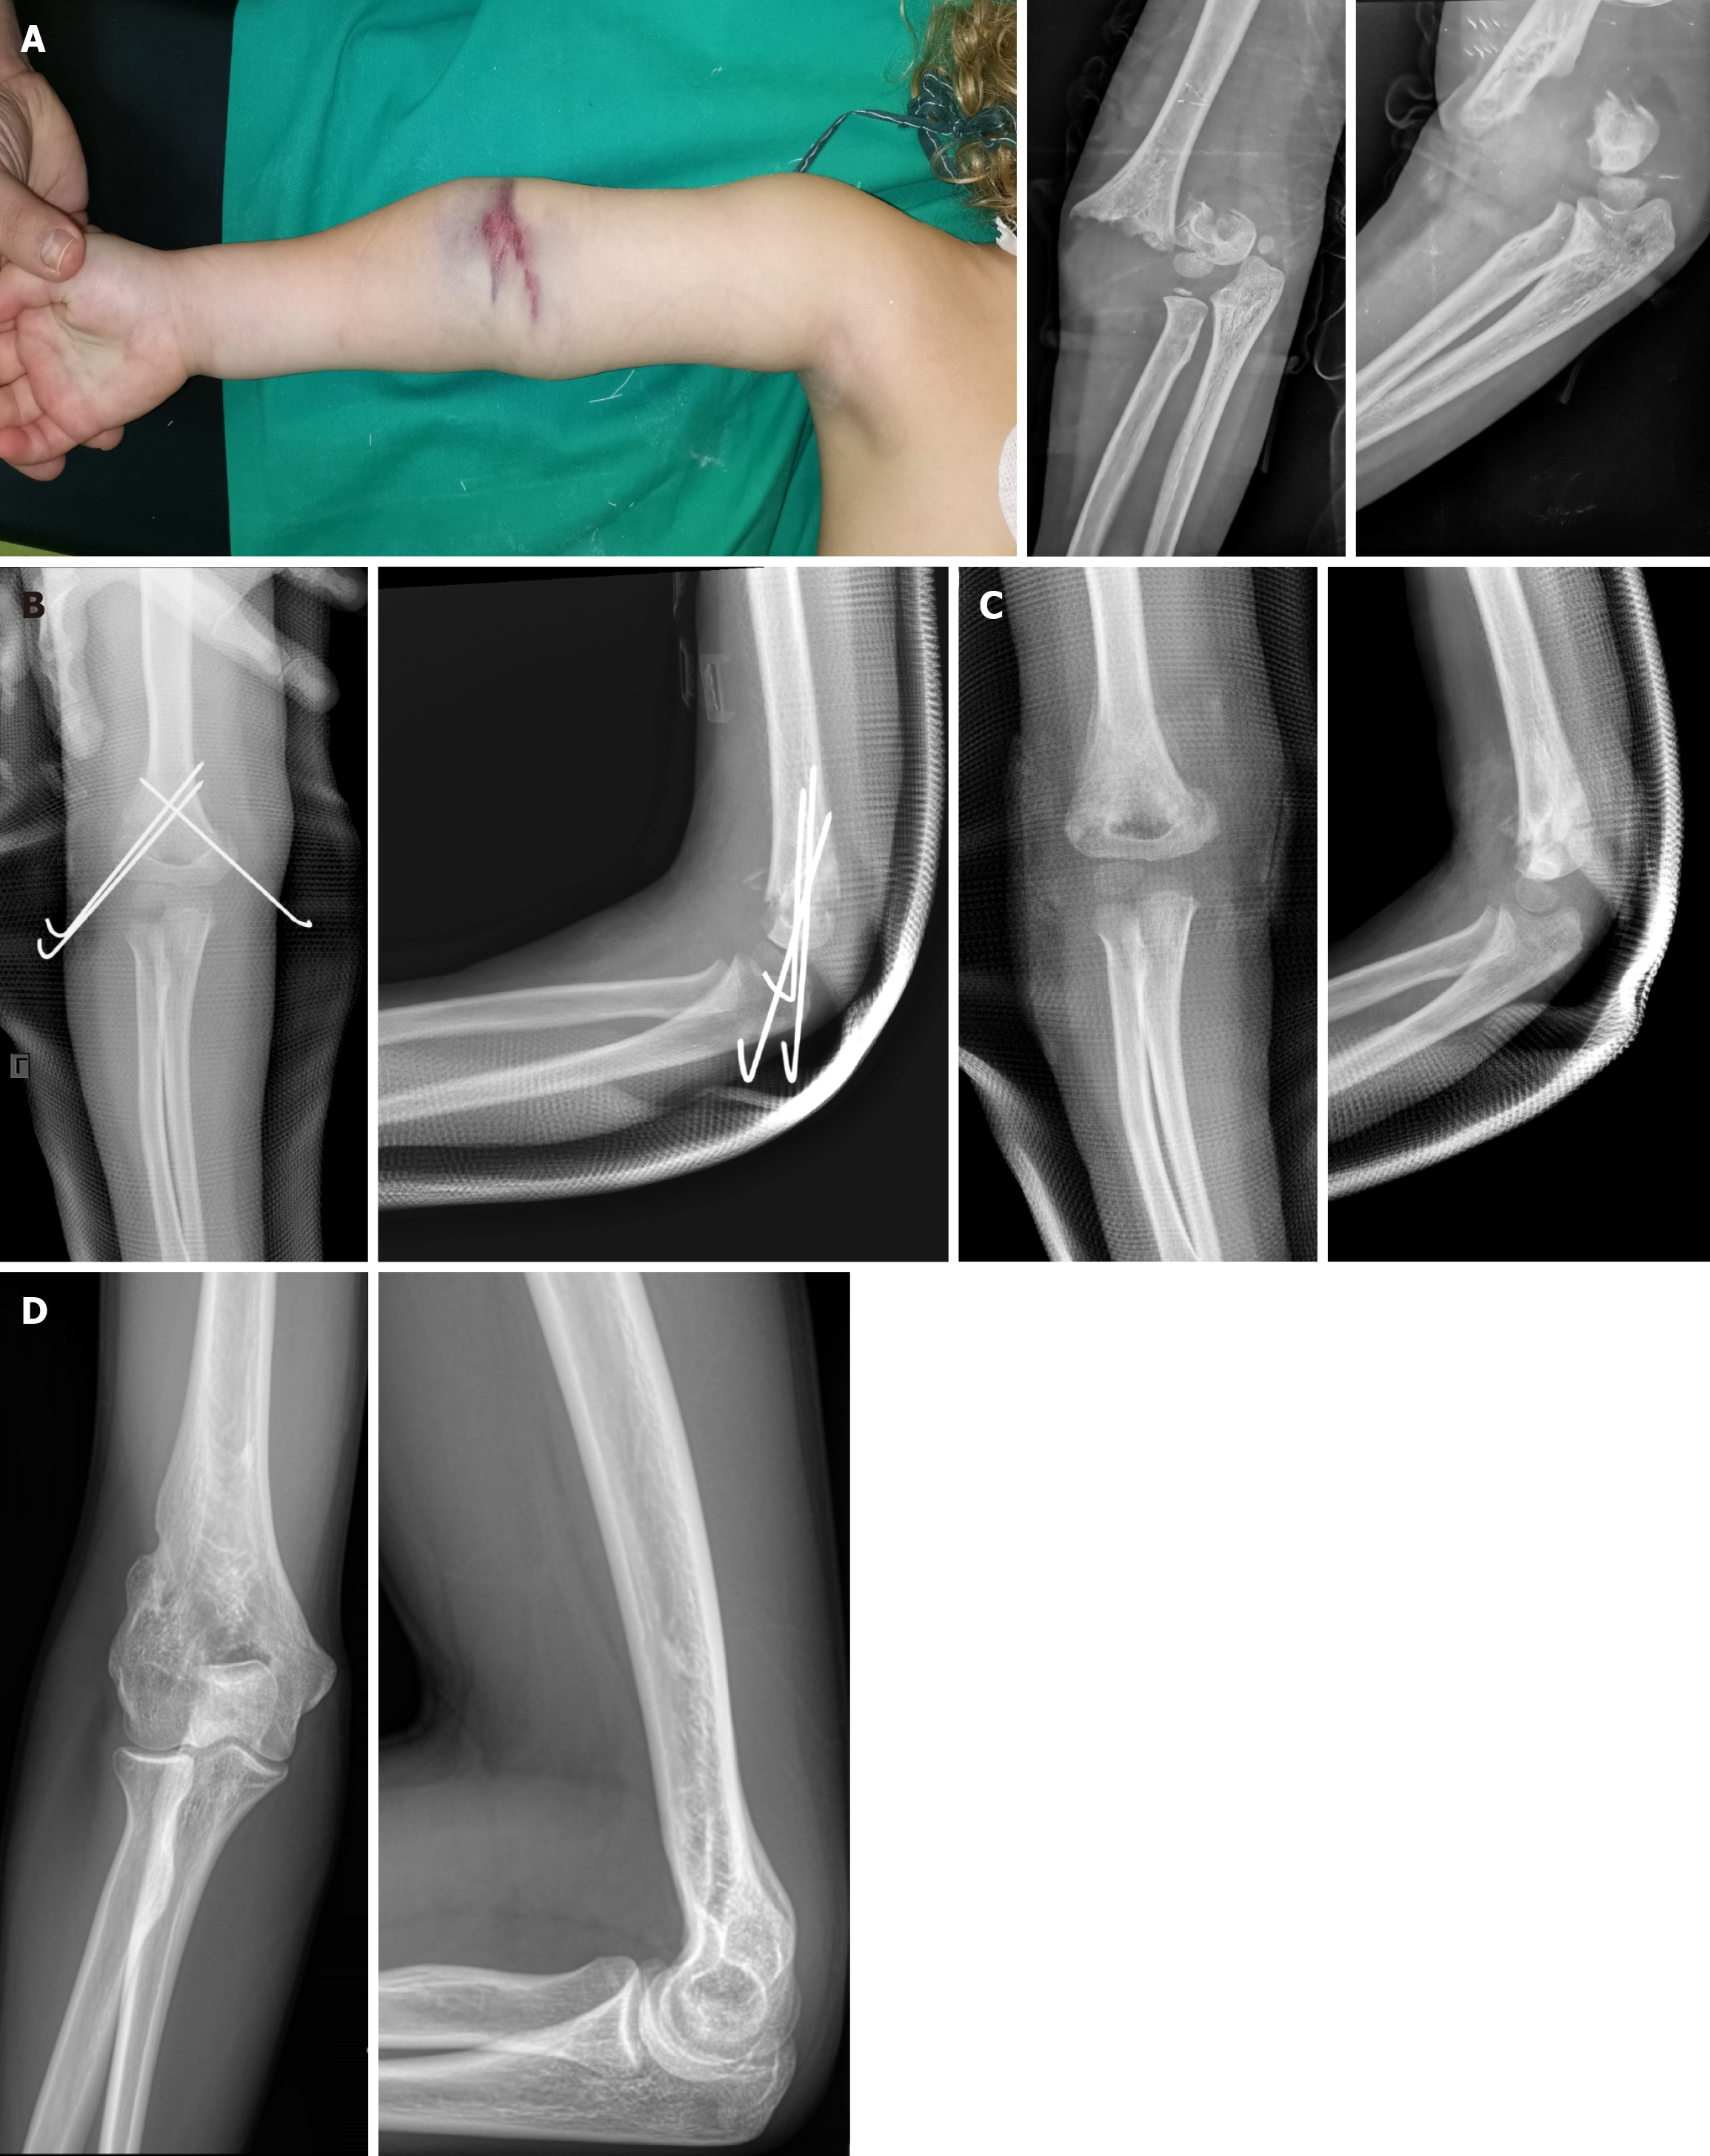

Figure 1 Typical ecchymosis in elbow fossa often suggesting vascular injury in a 4-year-old female with a right supracondylar humeral fracture of type IV according to modified Gartland classification.

A: Clinical and radiological presentation; B: The fracture was fixed after open reduction by lateral and medial approach; C: The K-wires were removed 1 month post-operatively; D: Right elbow X-rays at the age of 19 years.